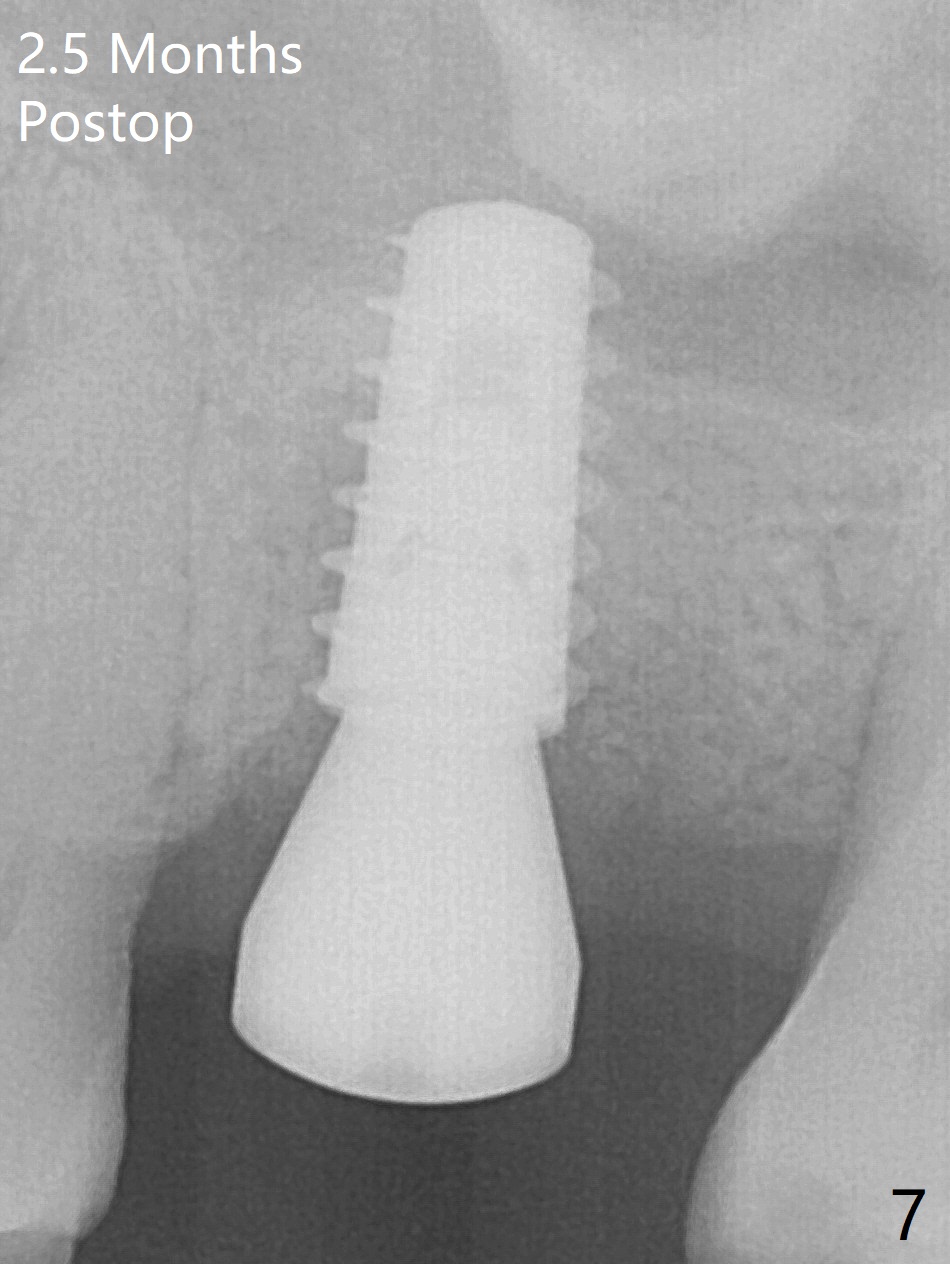

After extraction of the tooth #14 with palatal root fracture (Fig.1 <), sinus membrane perforation is found in the buccal wall of the palatal socket (Fig.2 ^). Osteotomy is initiated in the buccal strut of the septum (Fig.3 *). As the osteotomy increases in diameter, it slides into the mesiobuccal socket (Fig.4). A 5x9 mm implant is placed slightly mesial; after placement of a 6.5x4(2) mm abutment and insertion of collagen plug in the palatal socket, Vera graft is placed in the remaining socket space (Fig.5 *). Nasal hemorrhage persists 1.5 months postop (Fig.6). The distal gingiva is slightly tender and erythematous; a 6x4 mm healing abutment is placed 2.5 months postop (Fig.7,8). Impression is taken after laser gingivectomy 3.5 months postop. The patient feels discomfort at the site 7 days post impression, although the gingiva heals after laser treatment. Two weeks after cementation, the mesial gingiva is mildly tender and the abutment screw is loose. A 6x3 mm healing abutment is placed. The abutment/crown is reseated 10 months postop (Fig.9).